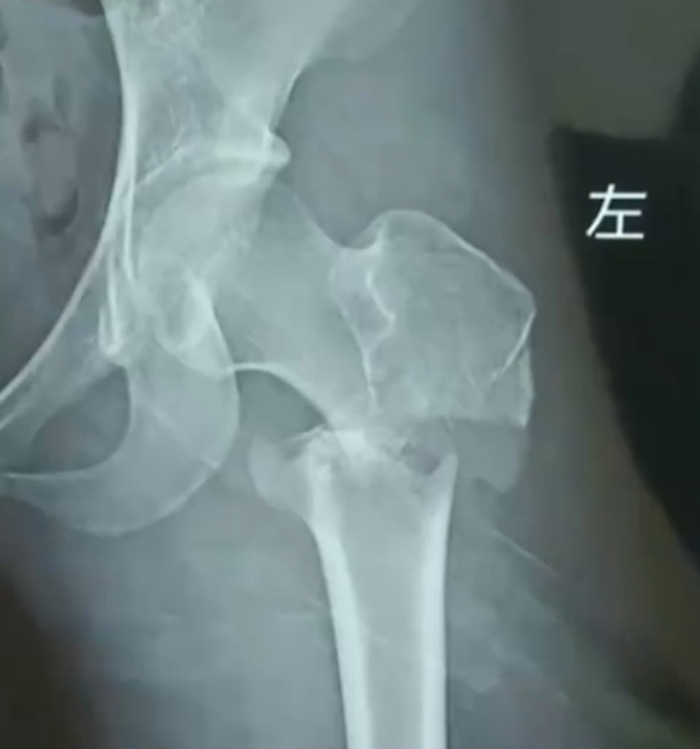

เรื่องราวนี้เกิดขึ้นกับเด็กสาว แซ่จาง วัย 17 ปี ซึ่งเข้าฝึกกับสถาบันสอนเต้นแห่งหนึ่งในฉงชิ่ง ประเทศจีน เมื่อวันที่ 25 มีนาคม 2566 โดยช่วงหนึ่งระหว่างที่เด็กสาวกำลังฝึกความยืดหยุ่นโดยมีกลุ่มผู้ฝึกสอนจับแขนขาเอาไว้ แต่กลับมีคนหนึ่งเหยียบค้างไว้ที่บริเวณด้านหลังต้นขาของเด็กสาวขณะกำลังถูกยืดตัว

เมื่อผ่านไปไม่กี่วินาทีก็เกิดเสียงหักดังสนั่นที่บริเวณขาข้างดังกล่าว เด็กสาวร้องกรี๊ดด้วยความเจ็บปวดและตกใจ แม้ว่าเธอจะถูกส่งตัวไปรักษาที่โรงพยาบาลอย่างเร่งด่วน แต่ดูเหมือนว่าอาการจะเลวร้ายมาก ต้องเข้าผ่าตัดถึง 2 ครั้ง และไม่สามารถเต้นได้อีกต่อไป